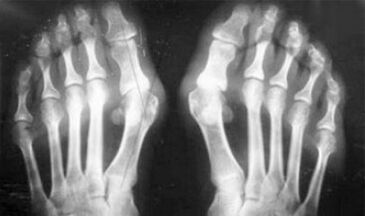

The difference between arthritis and arthritis of the fingers and hands of the hands is that the first disease is cured and the second is not.With arthritis, the synovial shells and the union capsule are touched.

Loss of cartilage and bone tissue occurs only in the late stages in a neglected state.With arthrosis, the cartilage tissue is first affected, and then the bone, the inflammation of the synovial membrane is of secondary origin, ie, it develops against their background.